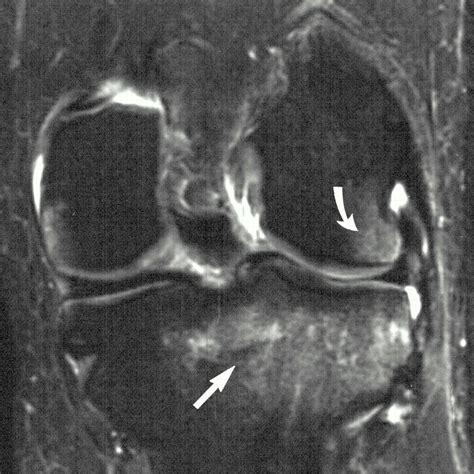

| MRI (Magnetic Resonance Imaging) | The gold standard for detecting edema and damage within the bone marrow. |

💡 Note: While X-rays are helpful to confirm the absence of a complete break, an MRI is strictly necessary to visualize the internal fluid buildup indicative of a bone contusion.

The severity of a bone bruise is generally categorized based on the location and the volume of the fluid accumulation. Common areas affected include the femoral condyles and the tibial plateau, which act as the main weight-bearing surfaces of the knee joint. Because these areas are subject to constant force during walking or standing, healing requires time and patience.